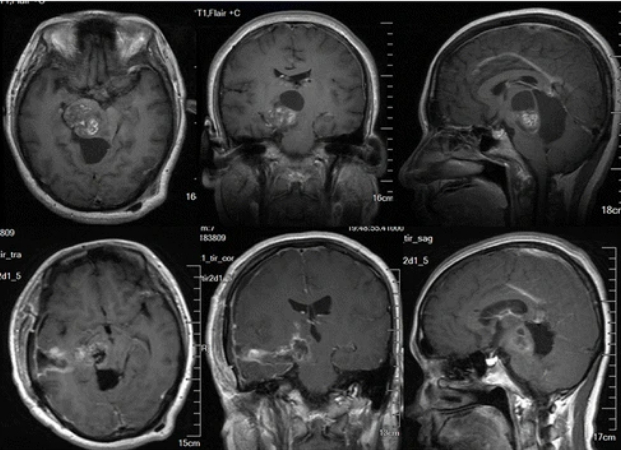

33岁的H女士在怀孕期间因严重头痛,走路不稳,记忆力减退等症状就医,MRI图像显示在她的两个侧脑室后部有一个较大的囊性肿瘤,立即进行囊肿排空和肿...